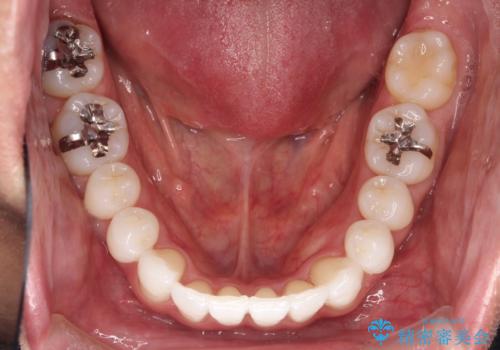

右上の前から2番目の歯が引っ込んで、下の前歯にはガタガタがありました。

上下の歯と歯の間を少量ずつ削りスペースを作り、インビザラインにて並べる計画としました。

目立たずに矯正治療を終えることができたことに満足していただけました。